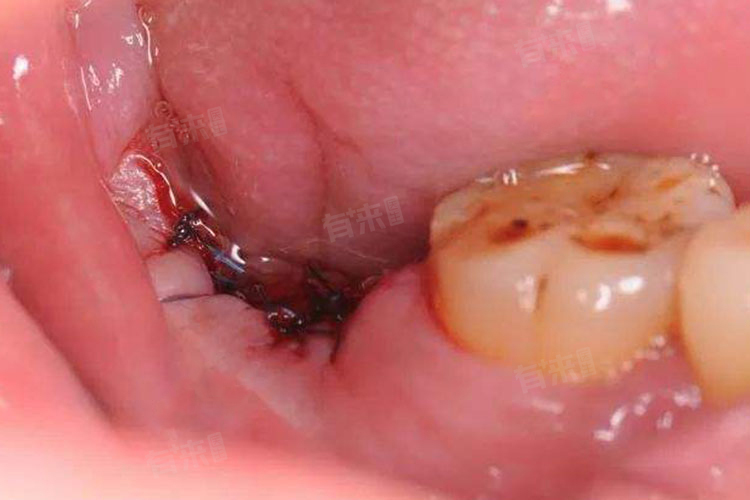

干槽症,也称为牙槽骨炎或牙槽窝干燥症,是一种拔牙后可能出现的并发症,通常发生在下颌智齿拔除之后。干槽症通常不能自愈,干槽症的特点是血凝块在拔牙窝内未能正常形成或者过早脱落,导致骨头暴露于口腔环境中,引起剧烈疼痛,并可能伴有口臭和异味等症状。

3、空虚感:患者在用舌头触碰拔牙部位时,可能会感觉到一个异常的空洞,这是因为原本应被血凝块填满的空间现在变成了一个开放的坑洞。